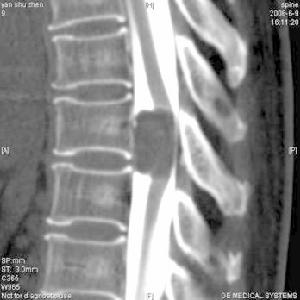

椎管造影

1.椎管造影是利用水溶性碘劑等顯影劑,注入蛛網膜下腔,操作後及時行X線片或CT等檢查以顯示其中病變的檢查法。多在腰3—4或腰4—5間隙進針,腦脊液流出後即緩慢持續注入造影劑。

2.椎管造影術適用於腰段椎管占位性病變、椎間盤突出、椎管狹窄症、椎管畸形、脊柱退行性病變等等。

椎管造影又稱之脊髓造影(MyelograPhy),作為診斷報管內占位性病變和因創傷所致頸椎管形態變化以及與脊髓相互關係。椎管造影是一種常用和有效的檢查手段,目前多選用Omnipaque碘水造影劑。脊髓造影的意義是:

(2)確定病變節段水平和病變範圍:例如椎管狹窄的部位和範圍及損傷後椎管形態的變化,以此作為臨床治療前後的輔助判斷依據。

(4)CT掃描:為了增強脊髓與占位性病變相互之間的對比度,將水溶性造影劑注人蛛網膜下腔後,再進行CT掃描,又稱之為電子計算機脊髓造影體層掃描。可清晰顯示硬膜囊內、外的結構。